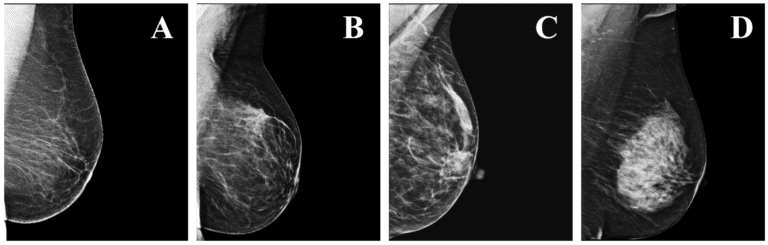

Mammogram

Women age 40 and older should have a screening mammogram every year and should continue to do so for as long as they are in good health. Mammograms for older women should be based on the individual, her health, and other serious illnesses, such as congestive heart failure, end-stage renal disease, chronic obstructive pulmonary disease, and moderate-to-severe dementia. Age alone should not be the reason to stop having regular mammograms. As long as a woman is in good health and would be a candidate for treatment, she should continue to be screened with a mammogram.